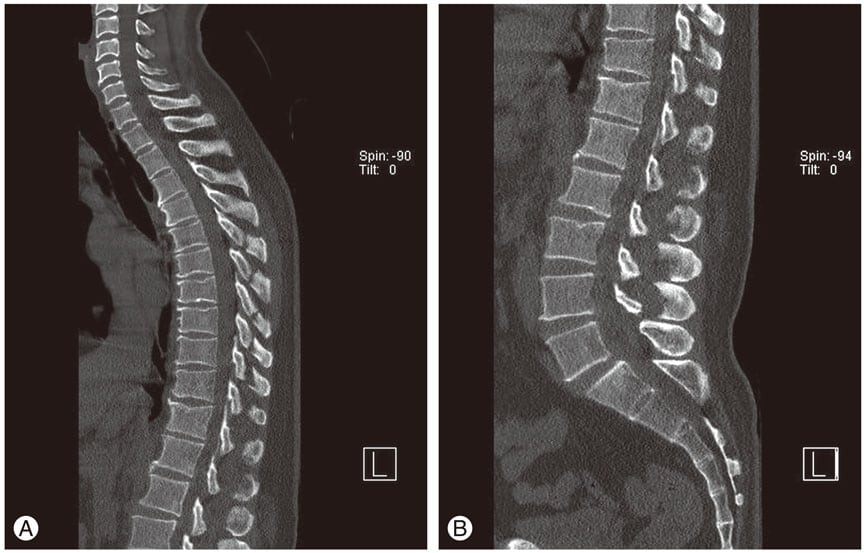

Хондрозом поражаются те отделы позвоночника, которые наиболее подвержены воздействию интенсивных статических и динамических нагрузок — шейный и пояснично-крестцовый. Грудные позвонки лучше защищены от деструктивно-дегенеративных изменений вследствие их крепления к ребрам. Независимо от локализации, патология имеет четко очерченную патоморфологическую картину.

Повышается и их чувствительность к механическим нагрузкам. Истончаются расположенные по периферии фиброзные кольца, в них образуются радиальные трещины. Сквозь них центральные части дисков (пульпозные ядра) постепенно смещаются к краям. В результате формируется протрузия, происходит выбухание межпозвонкового диска в позвоночный канал без разрыва фиброзного кольца.

По мере прогрессирования болезни механическая стабильность позвоночного столба восстанавливается. На его конечной стадии возникает защитно-компенсаторная реакция организма — начинают истончаться и патологически разрастаться края костных пластинок с образованием наростов — остеофитов. Одновременно утолщаются связки, наблюдается фиброз хрящевых тканей и капсул.